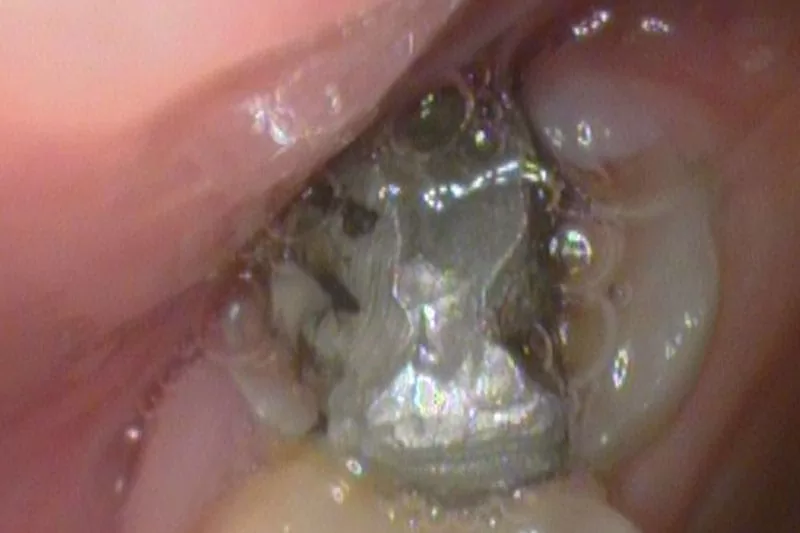

治療前剩餘齒質脫鈣逐漸崩落

一年前牙齒不舒服,經朋友介紹到某牙醫診所就診,因為左上第二大臼齒蛀牙深入神經,醫師告知須做根管治療,療程需每周安排一天一小時,為期約一個月左右,當醫師完成根管治療後,以銀粉將其缺口填補,大約經過半年時間,剩餘齒質逐漸崩落,於是我上網找到評價良好的-敦南麗緻牙醫診所,開啟前所未有的牙齒治療歷程。